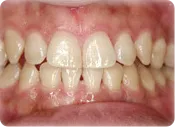

健康な歯肉

正常な歯茎の状態